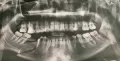

Прикрепленые фото

• Исходя из данного снимка, теоретически шины можно снимать, но неизвестна исходная картина, вид перелома и как быстро была оказана первая помощь. После снятия шин, ускорить восстановление функции челюсти поможет механотерапия, лечебная физкультура.